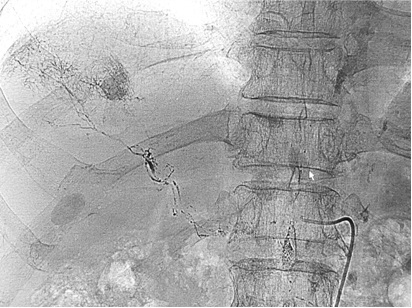

Incidental opacification of the deep lymphatic drainage pathway during PTC and TACE

![]() 胃切除后,顽固性腹水,低血清蛋白血症。经腹股沟淋巴结造影未见明显异常